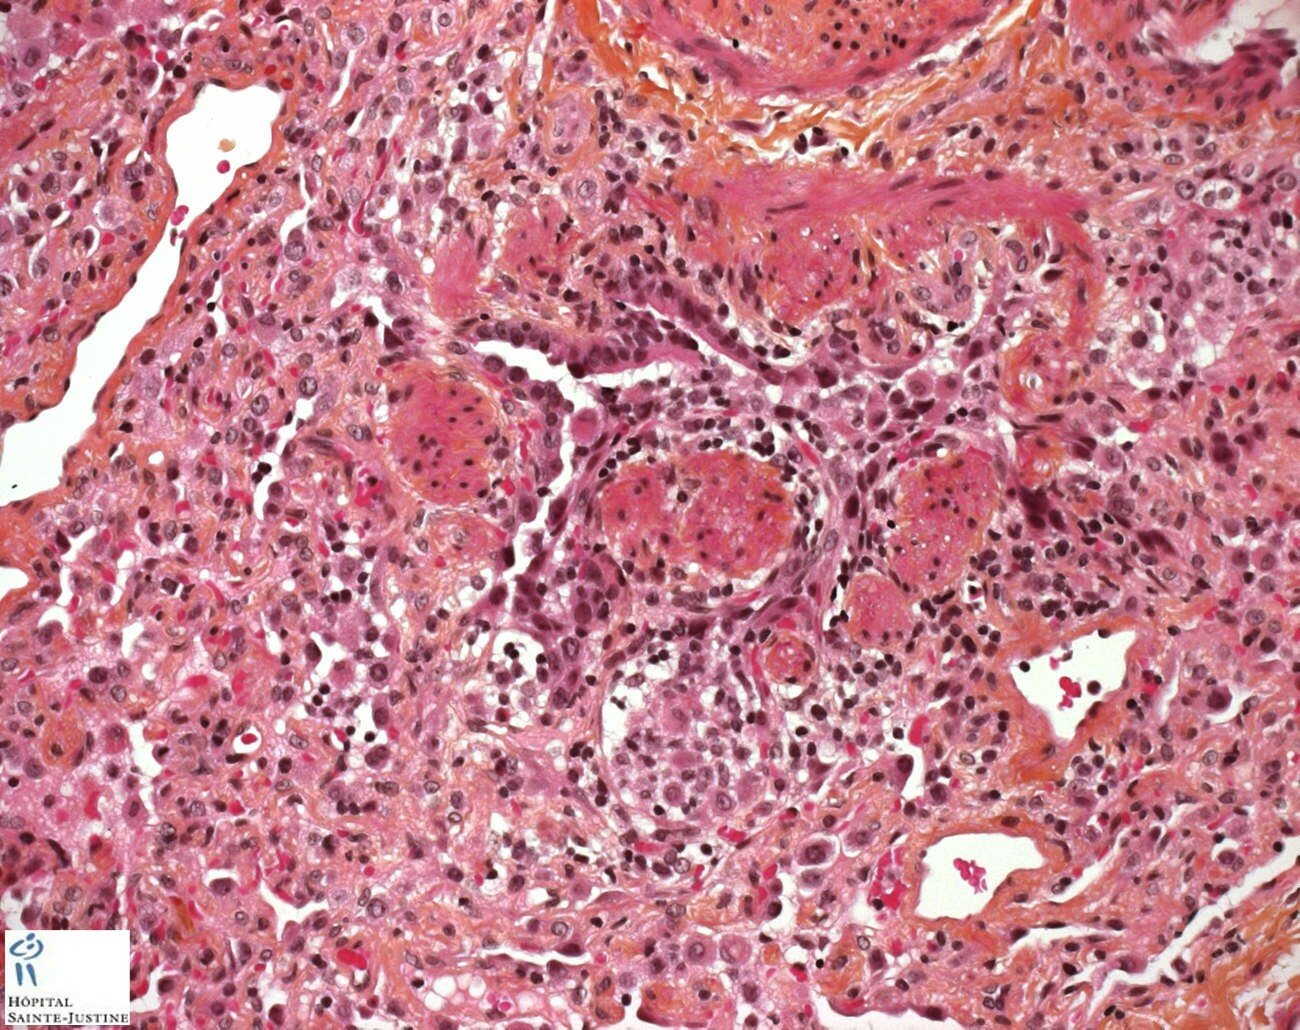

necrotizing bronchiolitis